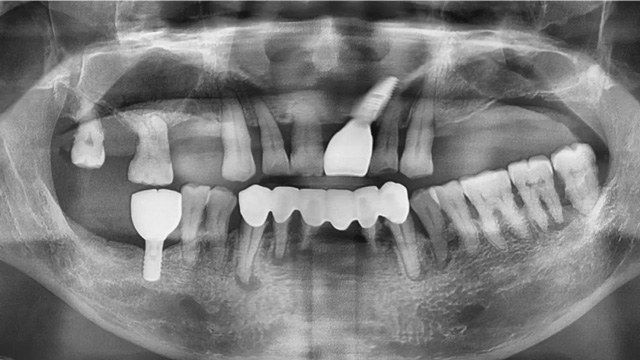

“周先生之前种过两颗牙,我为他保留了下颌的种植牙和上颌的种植体,做了上半口种植,下半口也做了两颗种植和联冠修复。”

李阳军医生介绍说,从咬合关系来说半口种植的难度比全口更大,因为全口是重新建立咬合,半口种植需要适应现有的牙齿,在选择种植位点、植入角度时需要考虑更多因素,对种植、修复两个环节的技术要求较高。

周先生半口种植前后全景片